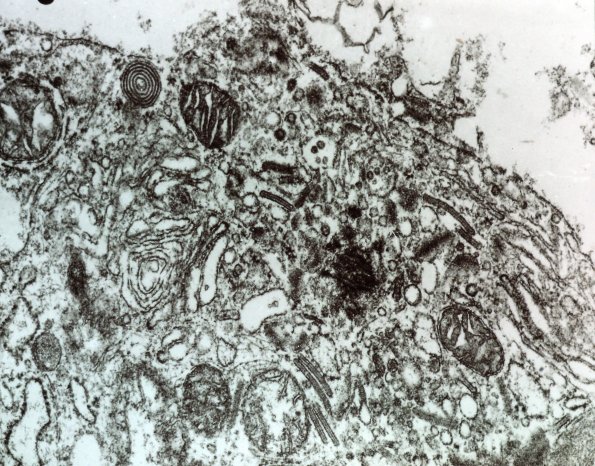

Dr. Ken Hashimoto

Histiocytosis